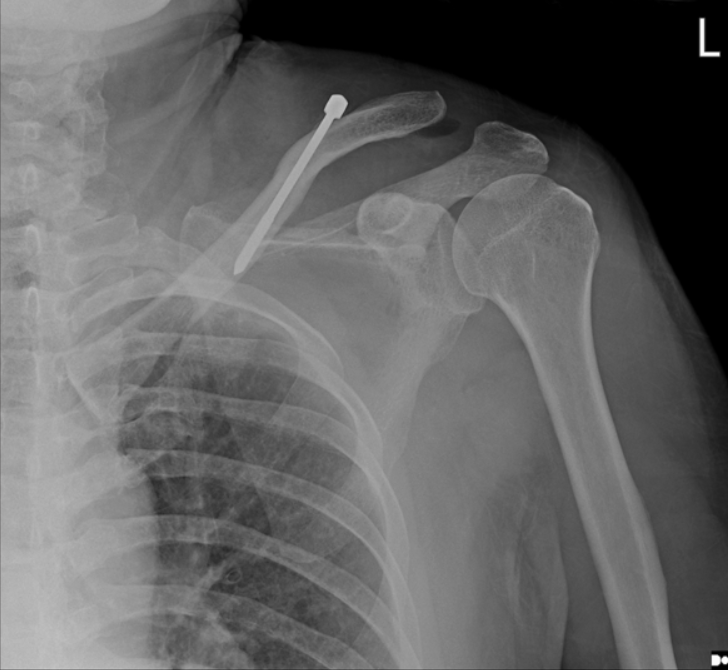

急诊就诊3天后门诊随访x线片显示锁骨中轴骨折倒v型移位

术后立即肩部x线片显示,锁骨骨折切开复位和Knowles针内固定后,肩锁关节(ACJ)明显移位。根据Rockwood分型诊断为V型ACJ脱位